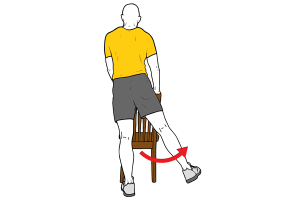

Escala y test de valoración muscular según Daniels & Worthingham’s.

“No me interesa tanto la mente humana como la maravilla de una naturaleza que es capaz de obedecer una ley tan simple y tan elegante